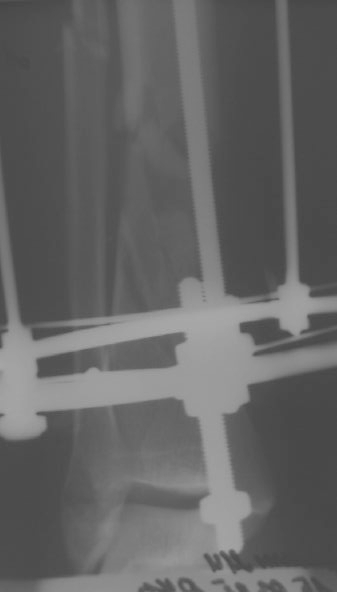

Больного прооперировал, обработку мягких тканей на голени не стал делать, думаю, некроз по краю швов на голени заживет под струпом (рис 3). На стопе удалил некротические ткани, готовлю ее к аутопластике (рис 2).

На дополнительных снимках итраоперационно видна значительная потеря массы (рис 6 рис 1). Хотя на снимках контрольных после операции вроде дефекта значительного нет. Все же придется, как-то замещать дефект костный на голени, думаю подготовить морально больного к повторной операции костной пластике, после заживления ран.